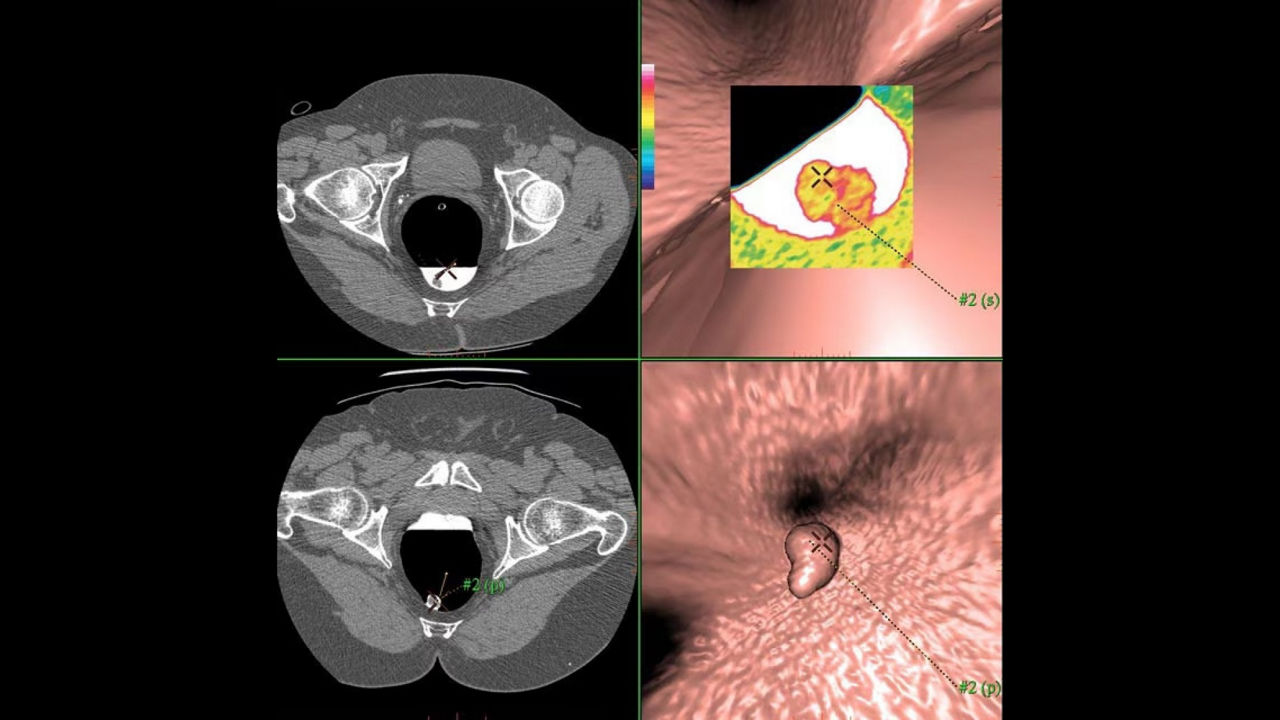

AdvantageCTC Pro3D EC

Efficient reading workflow solution for colonic lesion detection.

• Virtual biopsy tool aids problem solving in 3D views with colorcoded or black/white scales